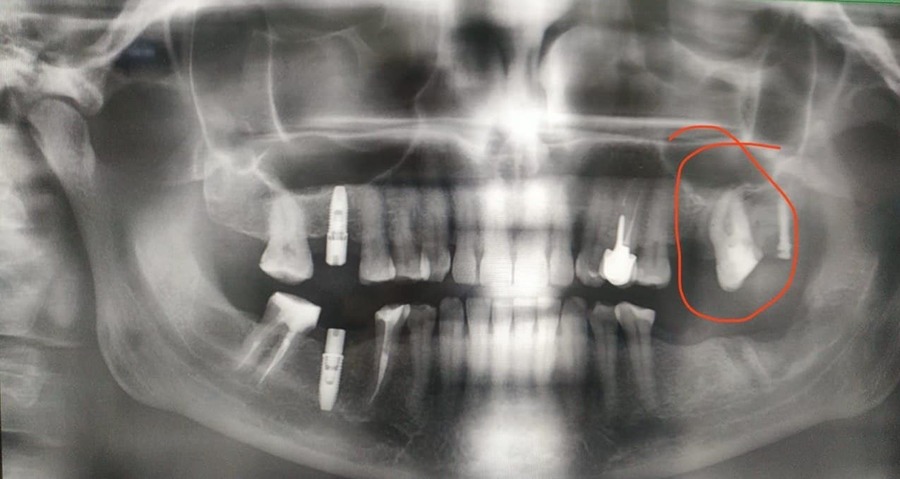

Что у нас было на входе? С правой стороны когда-то были удалены шестой и седьмой зубы, восьмой съехал на место седьмого. С левой — удалён шестой, седьмой с не очень удачно пролеченными каналами, в восьмом огромная полость. Шестой был удалён так давно, что седьмой практически полностью теперь на его месте. Восьмой лежит, не прорезавшийся. Тёмное пятно вокруг седьмого ничего хорошего не говорит, за корнем какая-то проблема локализуется.

Вернёмся к нашей пациентке, у которой процесс удаления восьмёрки стал, к сожалению, более травматичным, чем предполагалось. Врач принимает решение и репонирует отломанный бугор, привинчивая его ортоимплантом. Покажу на снимке: на верхней челюсти, где раньше был восьмой зуб, виден такой контрастный гвоздь. Вот это и есть ортоимплант.

Здесь получилось удачно: ортоимплант врач будет использовать не только как исправление ошибки с отломанным бугром, но и по прямому назначению — с его помощью зуб можно переместить или изменить его наклон. Если вдруг запутались, то напомню — седьмой у нас съехал почти полностью на место шестого, нужно его передвинуть на своё законное место, чтобы можно было ставить коронку шестого.

Как так получилось и почему не заметили раньше? Например, почему не увидели на снимке? Здесь нужно понимать, что рентген — это дополнительный метод диагностики. Мы получаем снимок и толкуем, что значат комбинации света и тени на нём. Не всё можно вовремя выявить на снимке — не всё будет очевидно читаться. Поэтому заметить раньше, к сожалению, у нас бы не получилось. Если сейчас, уже задним числом, когда мы знаем, что на этом зубе кариес, вглядеться в снимок и задаться целью найти его в этом самом месте, то можно будет разглядеть намёки. К сожалению, на практике не всегда так срабатывает, что всё можно увидеть заранее.

Тут у нас снова целый детектив: изначально седьмой зуб занимал половину места утраченного шестого зуба. Это произошло в том числе потому, что, когда прорезывалась восьмёрка, она, скорее всего, упиралась в седьмой зуб. Если бы шестой не удалили, то восьмёрка бы так и упиралась в седьмой. За это время зуб мудрости успел навредить седьмому, произошла резорбция костной ткани под влиянием такого сильного давления, и часть зуба опустилась под десну. Именно та часть, в которой развился глубокий кариес, была спрятана, и увидеть её стало возможным только после того, как удалили восьмёрку, ткани подтянулись, зуб выдвинулся немного из лунки и стало очевидно, что есть дефект. Неприятный и непредсказуемый.